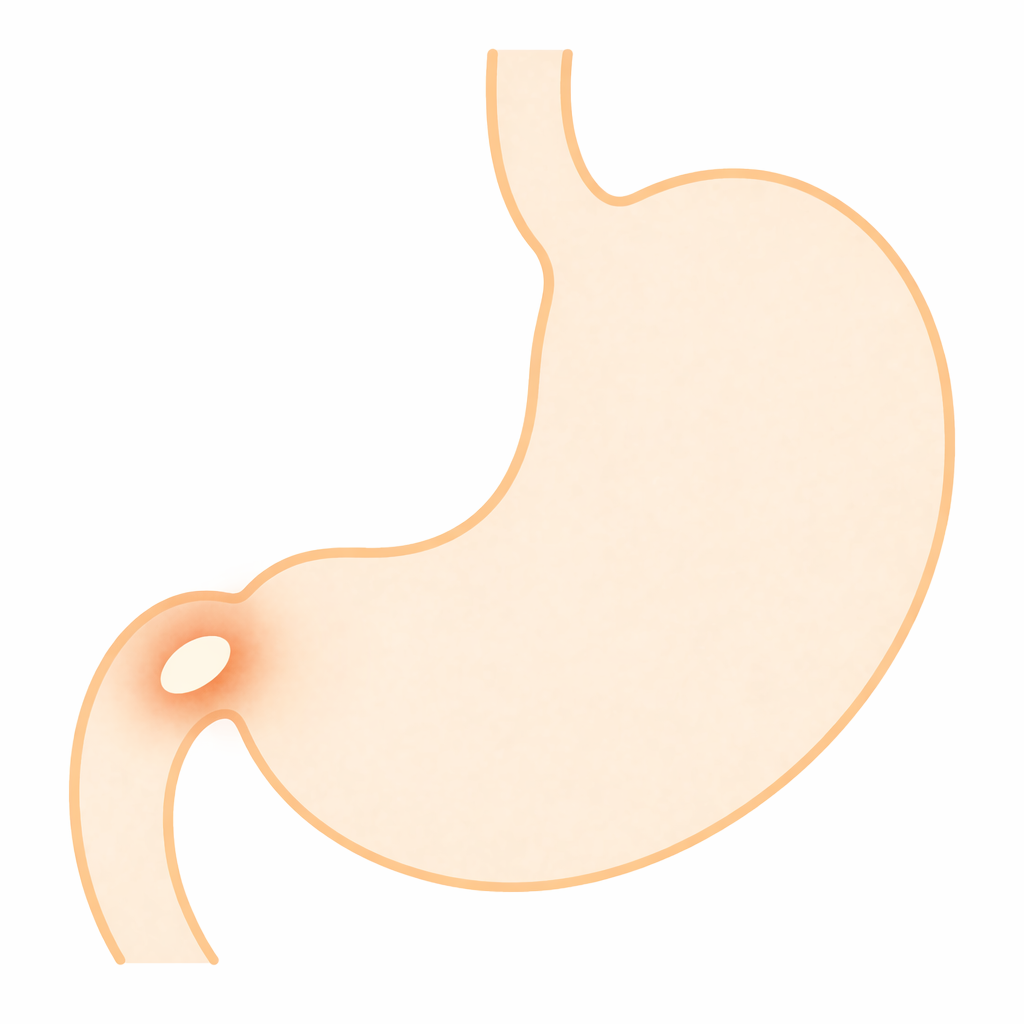

十二指腸潰瘍とは?

十二指腸潰瘍とは

十二指腸の粘膜が傷つき

深くえぐれた状態になる病気です。

主な原因は

・胃酸の影響

・ピロリ菌感染

・痛み止め(NSAIDs)

などです。

胃潰瘍と同じく

放置すると

出血や穿孔(穴があく)

につながることがあります。